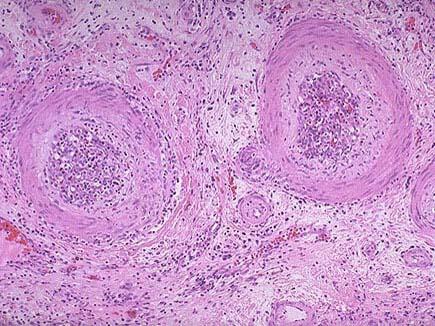

问题 某肾移植患者出现慢性排斥反应后治疗无效死亡,其肾脏镜下如图所示,关于慢性排斥反应的说法错误的是 ( )

选项 A.其突出的病变是血管内膜纤维化 B.肉眼观,肾体积明显缩小,并有多少不等的瘢痕 C.肾缺血是由于动脉内膜纤维化引起的管腔严重狭窄 D.患者肾功能呈进行性减退,但其程度与间质纤维化和肾小球、肾小管萎缩的程度不成正比 E.镜下可见肾小球毛细管袢萎缩、纤维化、玻璃样变,肾小管萎缩。

答案 D